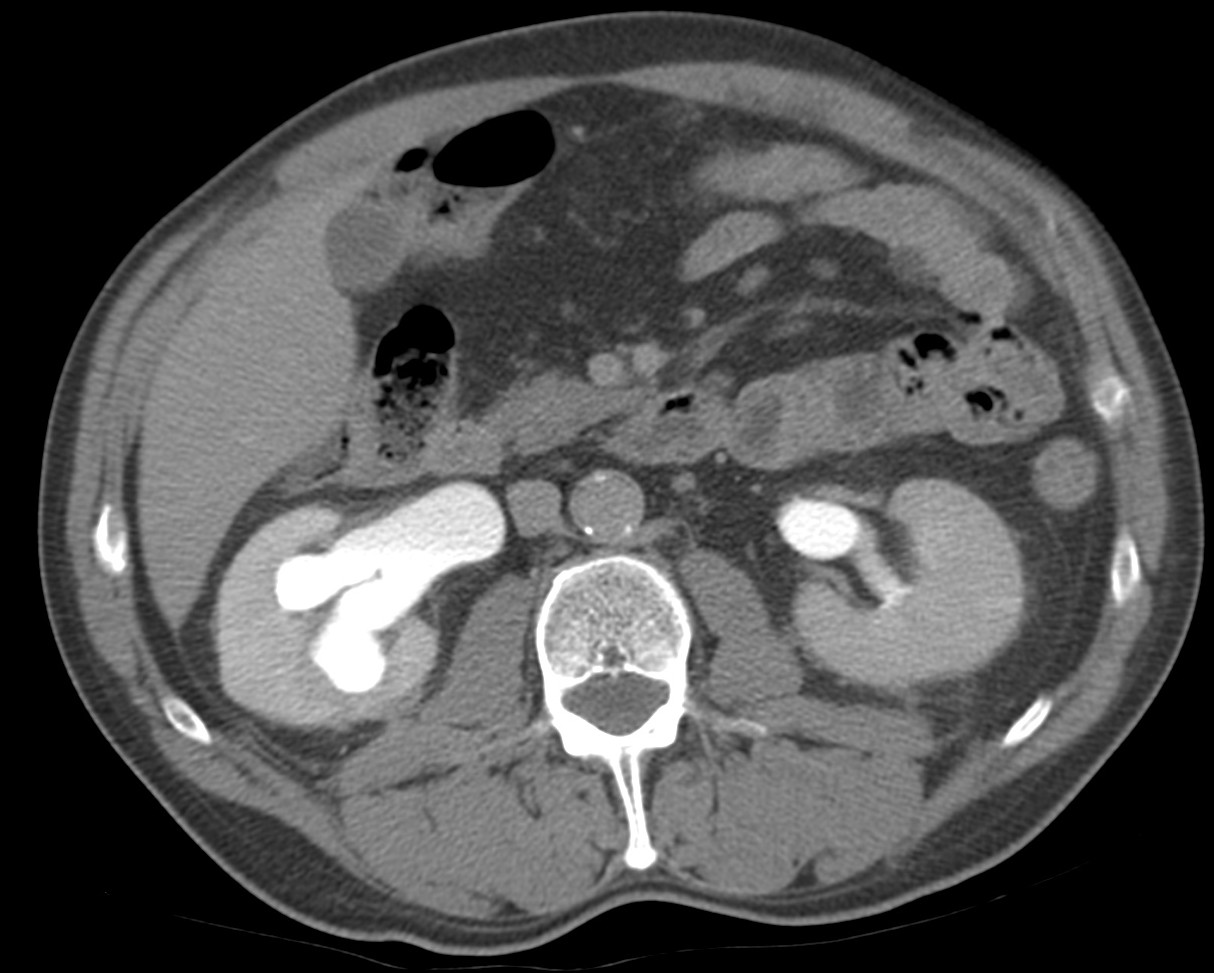

CASO CLÍNICO: Recopilatoción.

Paciente de 59 años con antecedentes personales de Cá de vejiga.

Se le realiza una Uro-Tc por seguimiento al año, aunque en esta ocasión el paciente refiere episodio de hematuria.

Tras el tratamiento de la recidiva y nefrostomía para la hidroureteronefrosis, vuelve acudir al hospital a los 9 meses por episodio de dolor en FD y malestar general. Se realiza una ecografía de urgencias.

Se realiza nueva TC bifásico abdominopélvio y Uro TC.

- Ha desarrollado un tumor metacrónico en pelvis renal derecha, también responsable de la hidroureteronefrosis.